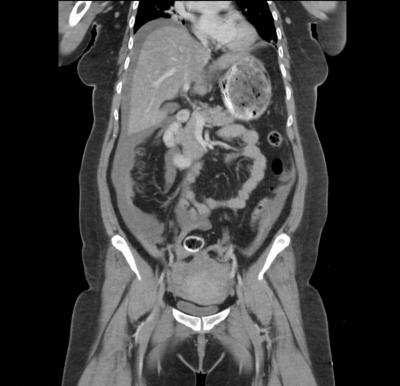

Ruptured Chronic Ectopic Pregnancy

Article |

December 28, 2021 - 4:10pm

| By

Bhasyani N

,

Shamsuriani MJ

NG BK

Janisha SR

Related Terms:

acute abdomen

chronic

ectopic pregnancy

emergencies

urine pregnancy test

Case report

kandungan ektopik

kecemasan

kronik

perut akut

ujian kehamilan air kencing